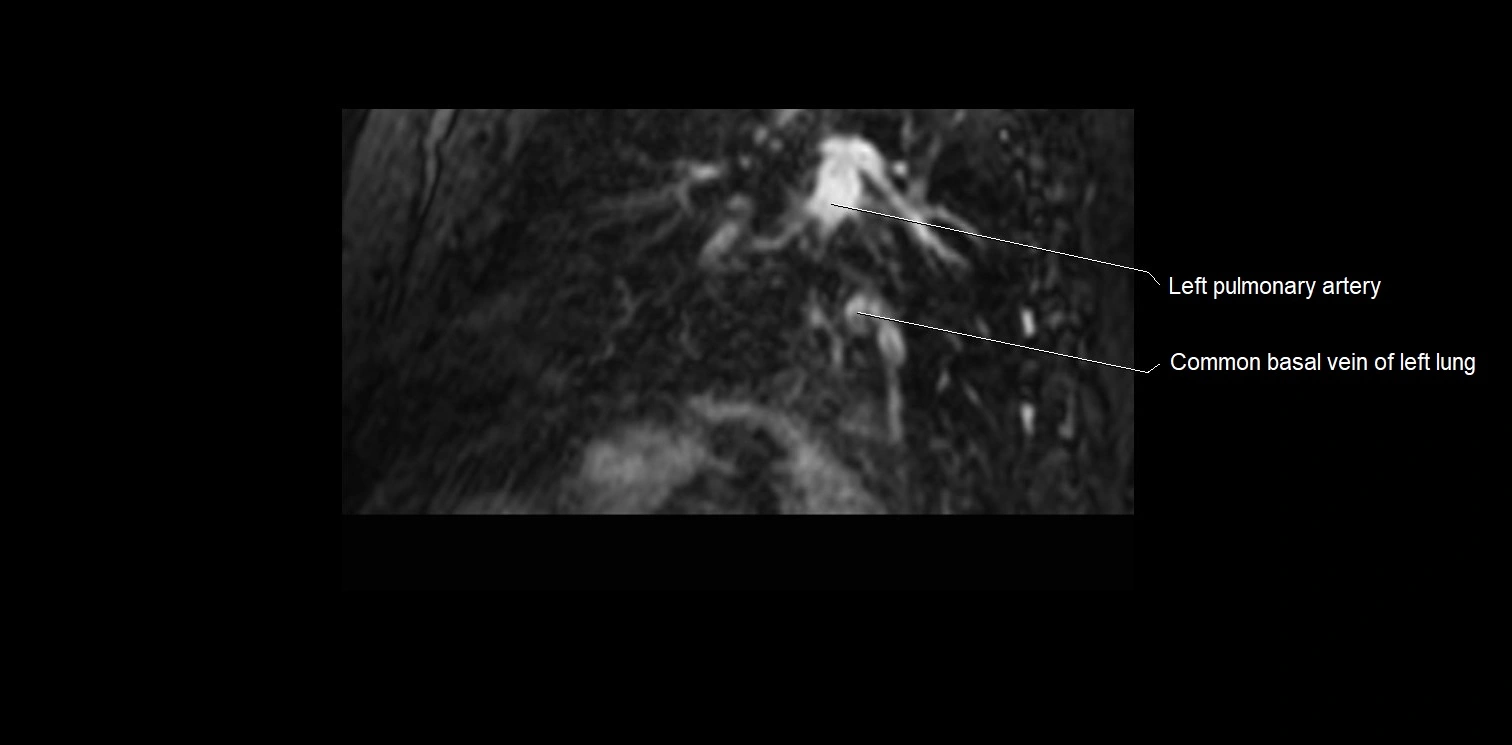

MRI image